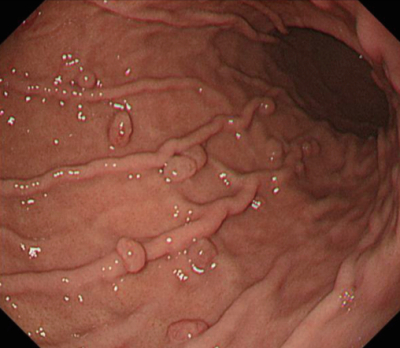

検査所見:尿所見:蛋白(-)、糖(-)、潜血(-)、沈渣に白血球を認めない。血液所見:赤血球400万、Hb 12.1g/dL、Ht 40%、白血球8,200、血小板30万。心電図と胸部エックス線写真とに異常を認めない。上部消化管内視鏡像を別に示す。

考えられる診断はどれか。

a. 胃GIST

b. 1型胃癌

c. 0-IIa型胃癌

d. 胃底腺ポリープ

e. 胃MALTリンパ腫